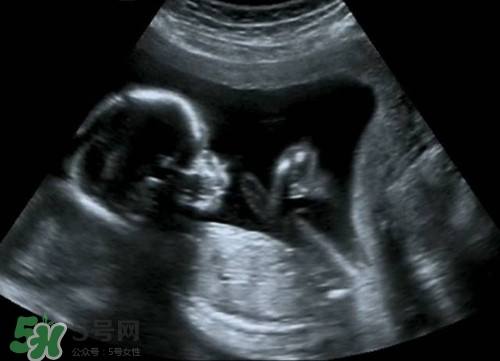

懷孕之后b超肯定是要做的,那么懷孕多久后可以做b超呢?做b超的話會(huì)影響到孩子嗎?下面我們來(lái)一起介紹下吧!

意見(jiàn)建議:孕期一般做3-5次B超,孕早期一次,目的是為了確定妊娠,估計(jì)胚胎發(fā)育,診斷孕早期常見(jiàn)疾病如宮外孕,葡萄胎,各種類型的流產(chǎn).孕中期也就是孕22-26周做四維彩超排畸篩查看看胎兒有無(wú)大體畸形及主要臟器畸形.孕晚期看胎兒,羊水及胎盤(pán)情況.

孕期做B超檢查是很有必要的.但是孕期做B超不要超過(guò)3次.一般是懷孕早期應(yīng)通過(guò)B超確定宮內(nèi)的妊娠是否正常.一般提倡于懷孕早期通過(guò)做B超明確是否是宮內(nèi)正常妊娠或雙胎,葡萄胎等.懷孕中期,大約在閉經(jīng)16周左右需要再做一次B超,以確定胎兒有無(wú)畸形和生長(zhǎng)發(fā)育是否正常.因?yàn)槿绻@時(shí)發(fā)現(xiàn)胎兒不正常,在閉經(jīng)20周以內(nèi)中止妊娠,是比較適宜的.懷孕晚期,即閉經(jīng)36周以后,做B超可以明確羊水多少以及胎盤(pán)的功能.羊水過(guò)多或過(guò)少,以及胎盤(pán)鈣化或功能不良,都不應(yīng)再繼續(xù)妊娠.必要時(shí)需進(jìn)行剖腹產(chǎn)

目前臨床上所應(yīng)用的B超,其探頭發(fā)射的聲強(qiáng)度小于10毫瓦/平方厘米,而且超聲檢查的時(shí)間往往只有5~10分鐘,對(duì)每個(gè)器官的探測(cè)時(shí)間更短.所以說(shuō),B超檢查對(duì)胎兒的危害是極小的,不會(huì)影響胎兒的身心發(fā)育.因此,孕婦不必對(duì)孕期B超檢查產(chǎn)生恐懼心理,適時(shí)的B超檢查是確保胎兒正常發(fā)育的重要手段.

正常情況下,妊娠早期應(yīng)進(jìn)行一次B超檢查,以明確是否妊娠,并確定妊娠的天數(shù).